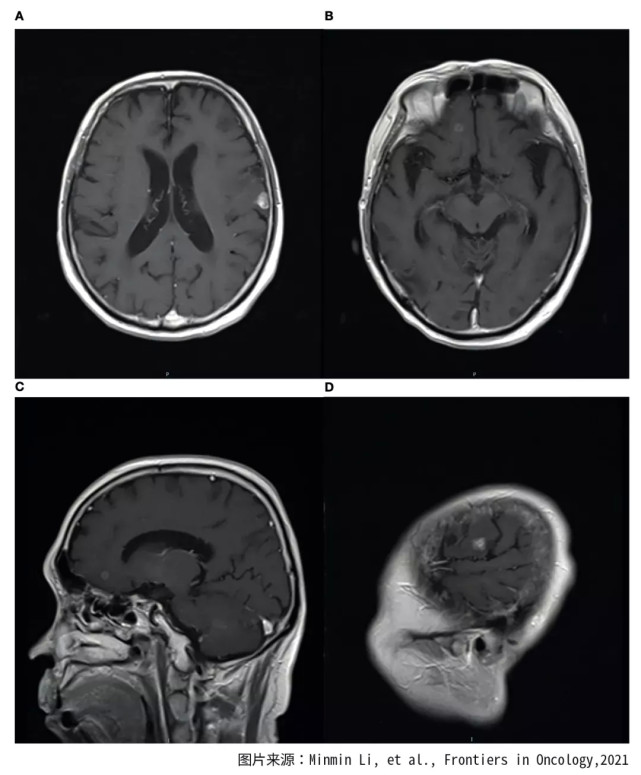

磁共振MRI检查表明肿瘤已经转移到脑部。由于脑部有多个转移灶,不能使用伽马刀治疗。患者属于四期肺癌,也失去了手术治疗的机会,医生建议患者使用化疗联合放疗作为治疗措施。

在进行了一个周期的吉西他滨联合顺铂的化疗后,对患者的原发病灶进行了放射治疗,使用的是二维放射治疗技术,总剂量为70格瑞,治疗分为35次。对脑部进行了全脑放射治疗,共20次分割,总放射剂量为40格瑞。

放疗之后,患者接受了三个周期的化疗,化疗用药为紫杉醇和顺铂。经过这些治疗,患者的症状明显减轻,血液的肿瘤标志物明显下降。放疗后的肿瘤病灶被评估为完全缓解(可见肿瘤病灶消失)。这种情况持续了近五年时间。